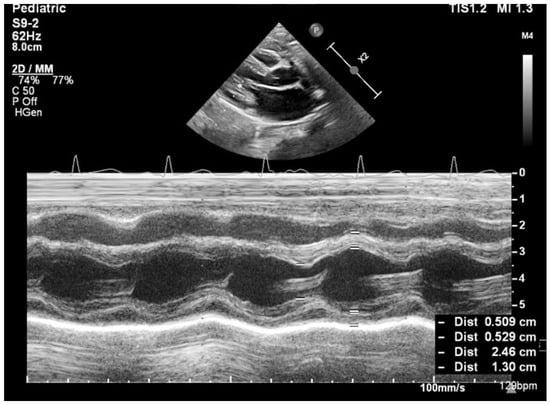

No complex congenital cardiac malformations were detected in the SMA cohort. Owing to thoracic deformities (common in the SMA), the left ventricular ejection fraction (EF) cannot be accurately measured via the Simpson method or strain rate studies; instead, fractional shortening (FS) was used to assess systolic function. All the children had normal systolic functions. Mild septal defects, such as patent foramen ovale (PFO) or small atrial septal defects (ASD), were observed. The left ventricular mass (LVM) percentile and left ventricular mass index (LVMI) significantly differed between the SMA and control groups. The median LVM percentile was 1.98% in the SMA group compared with 13.57% in the control group (p < 0.01). Similarly, the median LVMI was 50.54 in the SMA cohort and 56.27 in the control cohort (p < 0.01) (Figure 2 and Figure 3, Table 3).

Figure 2. Transthoracic echocardiography in an SMA type I patient (8 months old, 7.4 kg)—M-mode measurements (LVM = 14.24 g, p = 0.05%, Z score −3.27).